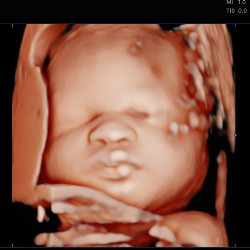

Being well-hydrated is crucial for getting clear 4D images. We recommend drinking two extra glasses of water per day in the week leading up to your scan. This helps increase the amount of amniotic fluid around your baby, making those precious face shots even clearer.

Good 4D images depend on your baby being in the right position. If necessary, we might ask you to wait in our comfortable waiting area for a short time while your baby moves into a better position. We’ll keep you refreshed with complimentary tea, coffee, and soft drinks.

- Stay Hydrated: Being well-hydrated is key for clear 4D images. Aim to drink two extra glasses of water per day in the week leading up to your scan to ensure there’s plenty of amniotic fluid around your baby.